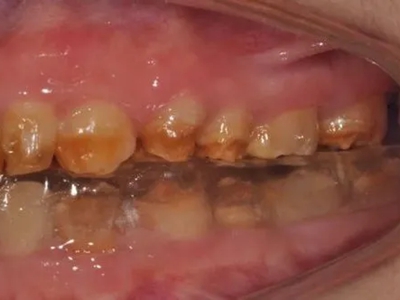

牙釉质发育不全牙表面上有坑图

牙釉质发育不全发展到严重时,导致牙釉质表面缺损,表现为带状、窝状的褐色凹坑,容易积存食物残渣诱发龋齿,表现为牙齿边上出现深褐色小洞。

牙釉质发育不全牙齿上棕色的坑图

牙釉质发育不全程度严重时,牙齿上出现较深的条状、点状凹陷,内含深褐色物质,并且牙齿尖端的牙釉质缺失,牙齿变得相对脆弱。